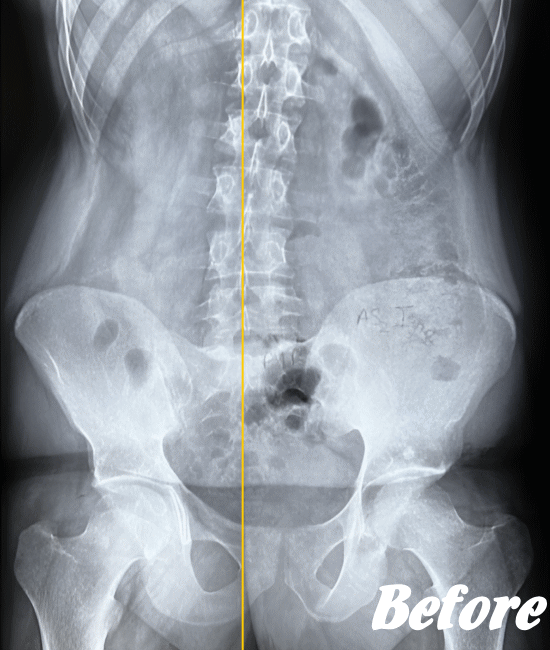

おそらく、ぎっくり腰を起こした状況や腰の状態から、筋肉や骨、椎間板、靭帯などのいずれかに障害が起きていると考えられるのですが、レントゲンなどの画像検査でも異常は認められないのです。

その中で、ぎっくり腰になった何人もの人の経緯を調べ、且つ、これまでの当院での施術経験からの一番の有力候補が、②の仙腸関節のズレであり、下図の「長後仙腸靭帯」に日常生活上のなんらかの動作により過大な負荷が加えられた結果、ぎっくり腰が発症するのではないかというものです。

実際、仙腸関節を調整しこの長後仙腸靭帯の緊張をリリースすると、著しい改善がみられています。ただし、あくまでヘルニアや狭窄などの他の腰の病気がない場合に限ります。